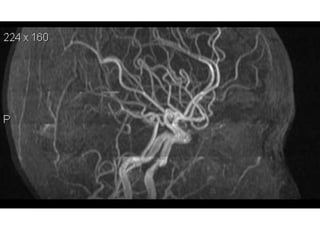

NORMAL MRA

Arteries of the brain (lateral view) - MRA

Arteries of thebrain (cranial view) - MRA 1. Anterior cerebral artery 2. Anterior communicating artery 3. Basilar artery 4. branches (in insula) of middle cerebral artery 5. Cavernous portion of internal carotid artery 6. Cervical portion of internal carotid artery 7. Genu of middle cerebral artery 8. Intracranial (supraclinoid) internal carotid artery 9. Middle cerebral artery 10. Ophthalmic artery 11. Petrous portion of internal carotid artery 12. Posterior cerebral artery 13. Posterior cerebral artery in ambient cistern 14. posterior cerebral artery in interpeduncular cistern 15. Posterior communicating artery 16. Posterior inf cerebellar artery. 17. Quadrigeminal portion of posterior cerebral artery 18. Superior cerebellar artery 19. Vertebral artery

Arteries of thebrain (lateral view) - MRA 1. Anterior cerebral artery 2. Anterior communicating artery 3. Basilar artery 4. branches (in insula) of middle cerebral artery 5. Cavernous portion of internal carotid artery 6. Cervical portion of internal carotid artery 7. Genu of middle cerebral artery 8. Intracranial (supraclinoid) internal carotid artery 9. Middle cerebral artery 10. Ophthalmic artery 11. Petrous portion of internal carotid artery 12. Posterior cerebral artery 13. Posterior cerebral artery in ambient cistern 14. posterior cerebral artery in interpeduncular cistern 15. Posterior communicating artery 16. Posterior inf cerebellar artery. 17. Quadrigeminal portion of posterior cerebral artery 18. Superior cerebellar artery 19. Vertebral artery